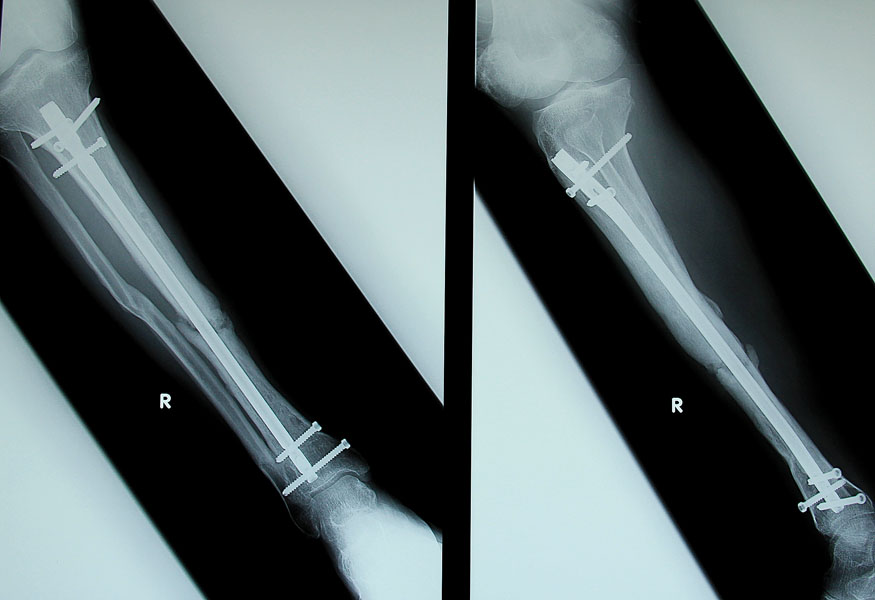

Obecnie urazy więzadłowe, łąkotek i struktur kostnych kolana stanowią razem około 30-40 % wszystkich urazów narciarskich. Początkowo najczęstszymi urazami w narciarstwie były urazy kończyn dolnych (złamania kostek i goleni, skręcenia stawu skokowego). Zmieniło się to w następstwie rozwóju sprzętu narciarskiego, szczególnie wiązań i butów narciarskich, które teraz automatycznie uwalniają nogę narciarza, gdy działają na nią zbyt duże siły. Niestety, nowe rozwiązania nie dały ochrony kolanom. Skręcenie więzadła pobocznego przyśrodkowego, więzadła krzyżowego przedniego (ACL), złamanie głowy kości piszczelowej i urazy łąkotki są obecnie największym zagrożeniem dla miłośników białego szaleństwa.